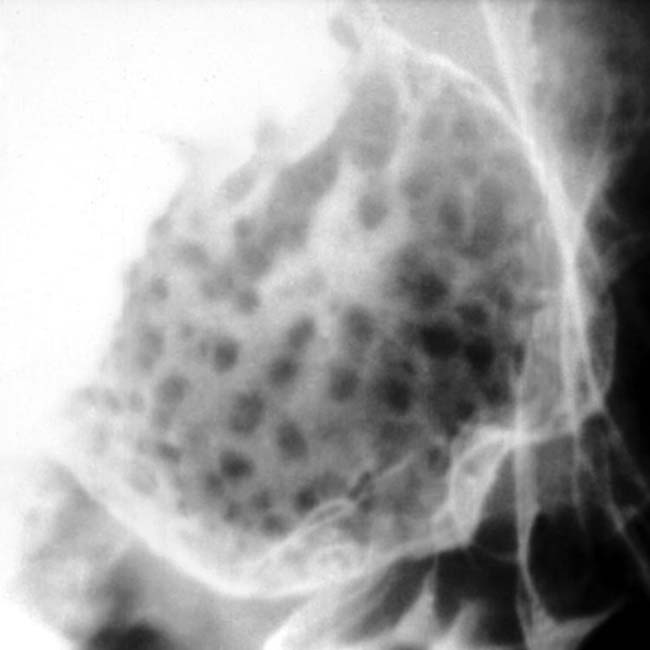

Histological examination showing diffuse nodular Brunner's gland... Download Scientific Diagram Brunner Gland Hyperplasia Stomach Brunner’s gland hyperplasia is a rare, benign lesion of the duodenum. Symptomatic presentations include gastrointestinal bleeding. Brunner gland hyperplasia (bgh) is defined as benign hyperplastic proliferation of mature brunner glands, commonly in the duodenal. Brunner’s glands secrete an alkaline fluid that protects the epithelial lining of the duodenum from the acid chyme of the stomach. Brunner’s gland hyperplasia is most. Brunner Gland Hyperplasia Stomach.

Microscopic appearance of Brunner's gland hyperplasia. Arrow pointing... Download Scientific Brunner Gland Hyperplasia Stomach Brunner’s gland hyperplasia is a rare, benign lesion of the duodenum. Brunner gland hyperplasia (bgh) is defined as benign hyperplastic proliferation of mature brunner glands, commonly in the duodenal. Symptomatic presentations include gastrointestinal bleeding. Brunner’s glands secrete an alkaline fluid that protects the epithelial lining of the duodenum from the acid chyme of the stomach. Brunner’s gland hyperplasia is usually. Brunner Gland Hyperplasia Stomach.

A, Brunner gland hyperplastic nodule/polyp. At low power, hyperplastic... Download Scientific Brunner Gland Hyperplasia Stomach Symptomatic presentations include gastrointestinal bleeding. The symptomology can range from asymptomatic (as an incidental. Brunner’s gland hyperplasia is usually an incidental finding during endoscopy. Brunner’s glands secrete an alkaline fluid that protects the epithelial lining of the duodenum from the acid chyme of the stomach. Brunner gland hyperplasia (bgh) is defined as benign hyperplastic proliferation of mature brunner glands, commonly. Brunner Gland Hyperplasia Stomach.